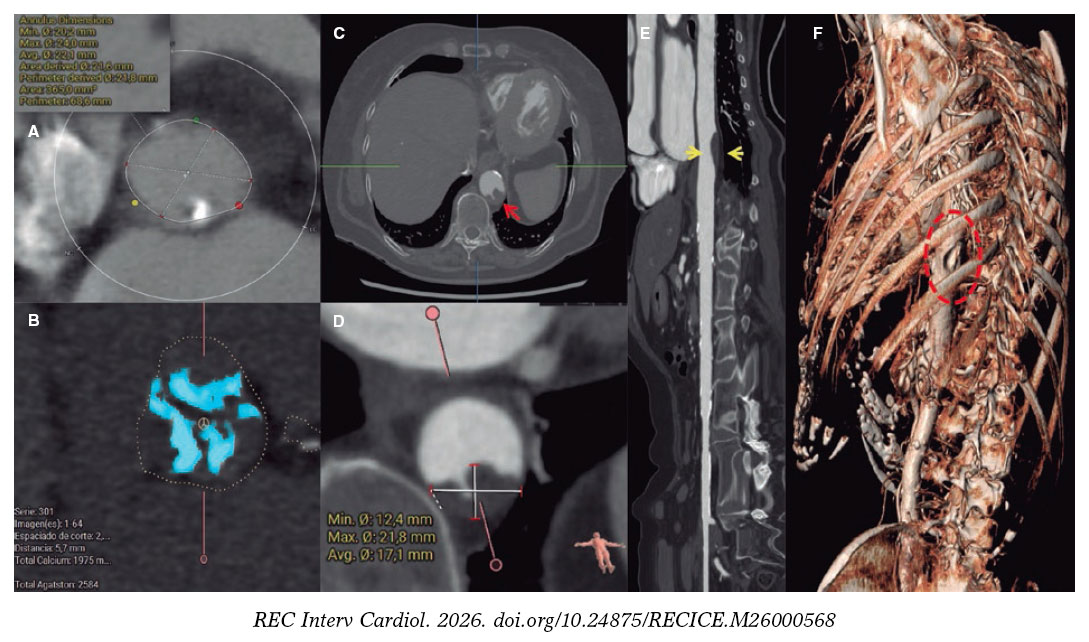

This is the case of an 86-year-old woman with symptomatic severe aortic stenosis. Prior to transcatheter aortic valve implantation (TAVI), coronary computed tomography angiography revealed the presence of an aortic annulus perimeter of 68 mm (figure 1A), severe valvular calcification of 2584 Agatston units (figure 1B), a 22 mm × 12 mm (figure 1D) soft plaque with an irregular surface in the descending thoracic aorta (figures 1C, E, arrows; figure 1F, ellipse), and adequate femoral accesses.

Figure 1.